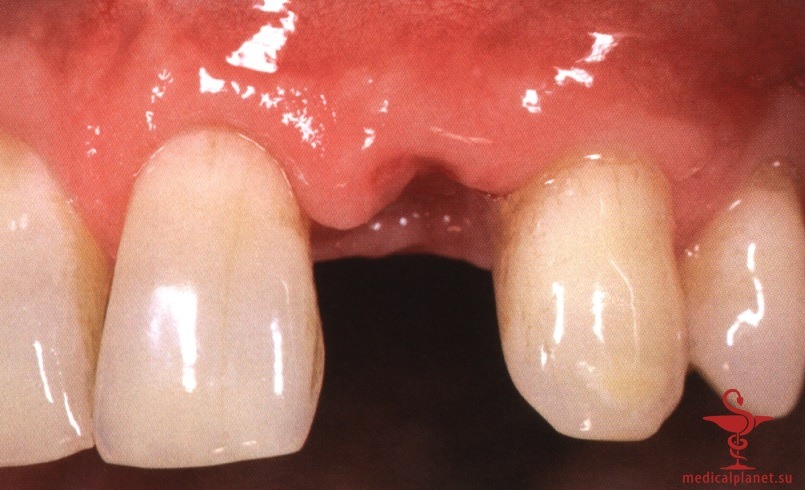

Сначала предполагалось, что уменьшение зазора является предпочтительным, поэтому рекомендовали устанавливать имплантаты максимального диаметра. Данное предположение оказалось ошибочным. В настоящее время доказано, что зазор менее 0,5 мм между костью и имплантатом заполняется новообразованной костной тканью без каких-либо дополнительных манипуляций.4 Более того, следует избегать контакта имплантата с костной стенкой, чтобы не оказывать на нее давление, которое сопровождается резорбцией кости (рис. 4).